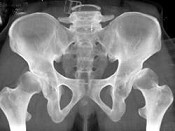

- 单项选择题男,23岁, 跛行,外展受限, 两下肢不等长,结合图像, 最可能的诊断是 ( )

A、髋关节中心脱位

B、髋关节后脱位

C、髋关节前脱位

D、先天性髋内翻

E、髋关节结核